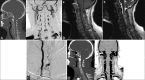

Patients and methods: In this report, we describe two unique cases of type I cervical spinal AVF, in which a radiculomeningeal artery forms an intradural fistula that drains into the ventral venous plexus.

Results: Both patients underwent surgical obliteration of the fistula with complete occlusion confirmed on postoperative angiography.

Conclusion: Both cases do not fit into the current classification scheme. A modified classification is proposed.